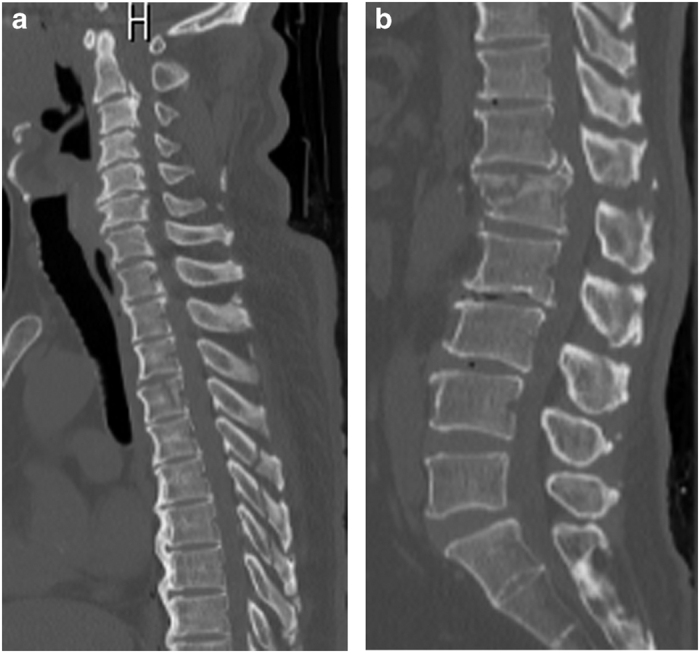

Figure 1.

Initial computed tomography (CT) revealed a T4 vertebral body fracture with minimal displacement, fractured thoracic spinous processes 5–7 (a), an L1 burst fracture with T12 anterior subluxation (b) and ankylosing spinal hyperostosis.